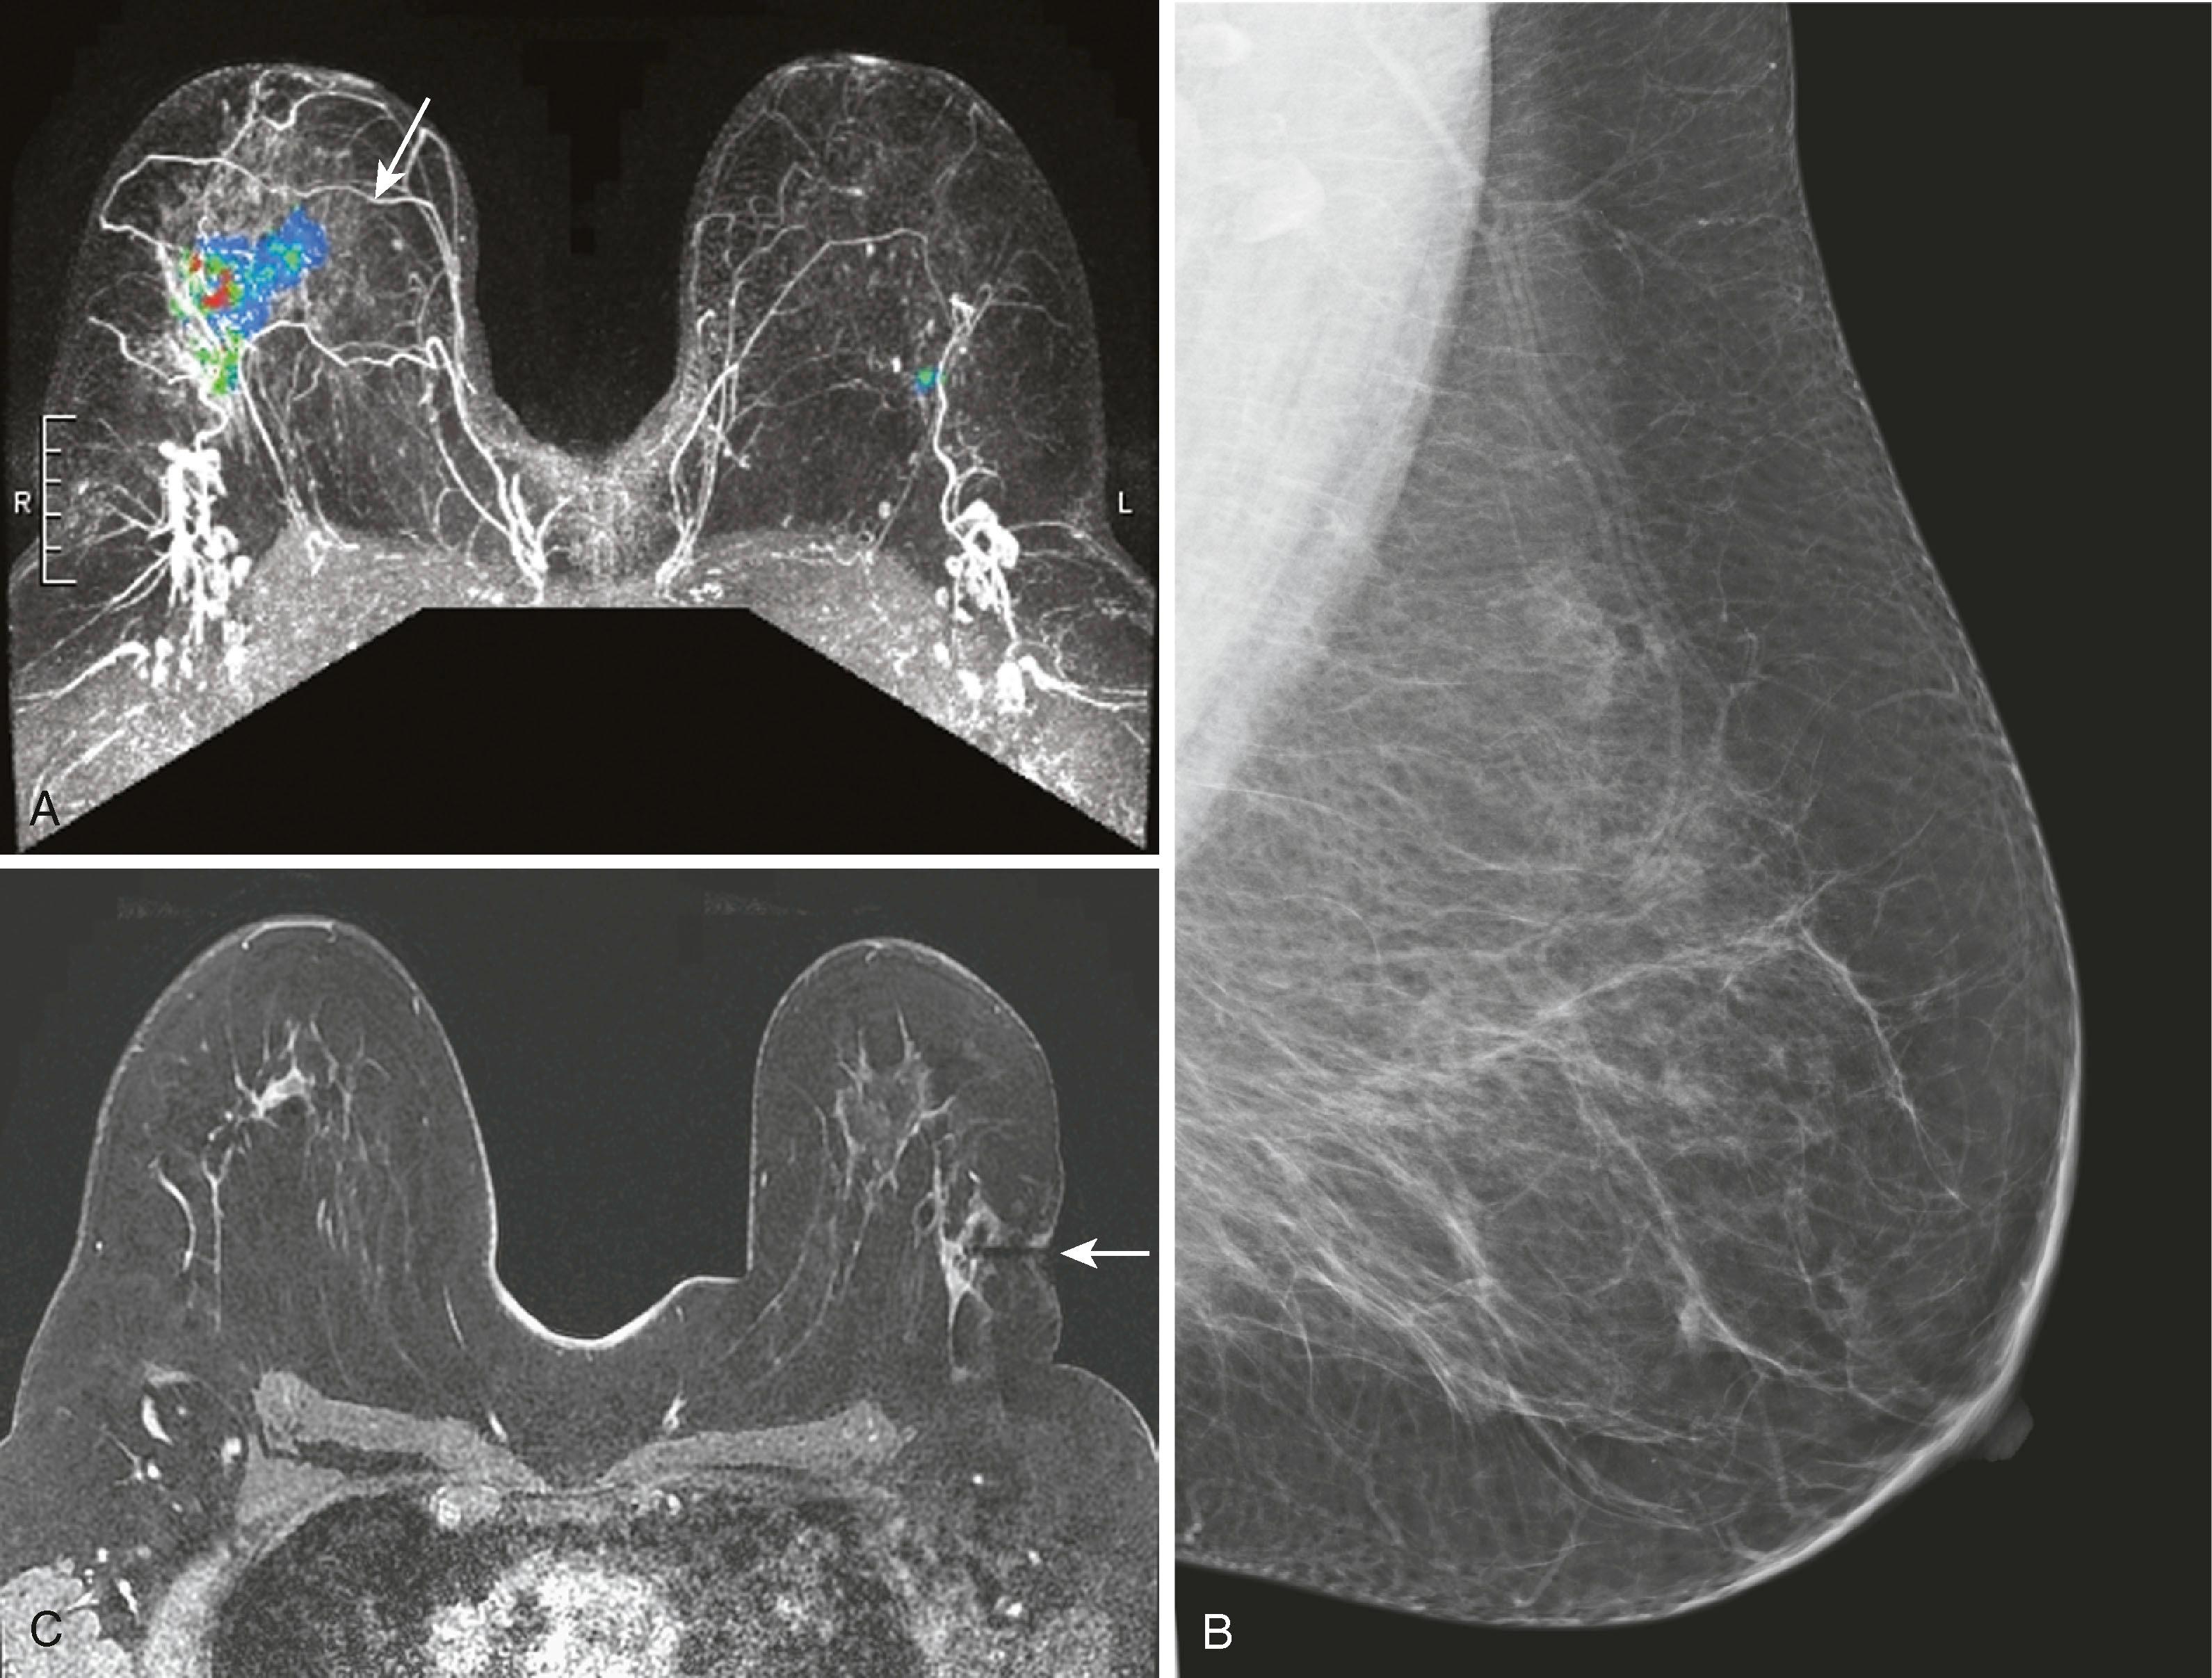

One of the most common uses of breast MRI is to evaluate for extent of disease in patients with biopsy-proven breast cancer. Liberman and associates, in a study across multiple series, reported that up to 48% of women with breast cancer will have unsuspected additional cancer that was not expected from mammography. This could be either multifocal or multicentric disease. MRI has been reported to depict additional tumors that necessitated wider excision in 27% to 34% of patients. Berg and coworkers point out that this closely mirrors the 25% to 36% rate of local recurrence in patients treated without chemotherapy or radiation therapy. MRI is relatively accurate at estimating tumor size but can overestimate and underestimate size on average by 15 mm in approximately 48% and 40% of findings, respectively. Because the size variation between MRI and pathological truth is relatively small, it is unlikely to have clinical implications. Lobular cancer is especially difficult to evaluate because it is well known that mammography, physical examination, and ultrasound tend to underestimate the extent and size of the tumors. Perhaps just as important, Lehman and colleagues reported that approximately 3% of women will have an unsuspected cancer in the contralateral breast ( Fig. 8.29 ).

Fig. 8.29, ( A ) Color maximal intensity projection from magnetic resonance imaging (MRI) examination shows a large invasive lobular carcinoma in the right breast (solid arrow) and contralateral ductal carcinoma in situ of the left breast. ( B ) Mediolateral oblique mammogram of the left breast demonstrates no abnormality. ( C ) Because the lesion could not be seen by ultrasound and mammography, MRI-guided biopsy was used when a biopsy was performed on the lesion. The needle guide is seen as a black signal void (arrow) .

Breast MRI has become the gold-standard test to search for a breast primary when a patient presents with a carcinoma of unknown primary. It is valuable not only because of its high sensitivity in identifying the primary tumor but also because of its high negative predictive value. Liberman and associates noted in a small study group of 16 women that MRI identified the primary breast tumor in 13 out of 16 patients. MRI may be of greatest value when a patient presents with axillary lymphadenopathy and a negative mammogram. Fig. 8.35 demonstrates such a patient who presented with axillary lymphadenopathy and a negative mammogram.

Fig. 8.35, A 42-year-old woman was noted to have prominent right axillary lymph nodes and had excisional biopsy of one of the lymph nodes, which revealed carcinoma. Her mammogram did not reveal the primary carcinoma. ( A ) Abnormal mammogram of the right breast. ( B ) Right axillary ultrasound demonstrates enlarged lymph nodes (arrow) . ( C ) Magnetic resonance imaging (MRI) demonstrates the right axillary adenopathy (arrow) . ( D ) MRI additionally demonstrates the occult primary breast malignancy (arrow) .